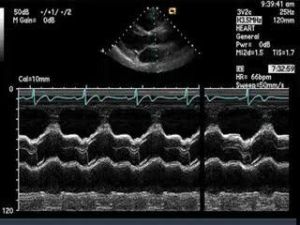

(4)2b區(右室、室間隔、左室)檢查法

①取樣線通過顯示有二尖瓣腱索的左室,從前到後之解剖結構為:胸壁及右室前壁、右室腔、室間隔、左室腔(左室腔內有二尖瓣腱索或二尖瓣前葉片斷回聲)、左室後壁。

②測量法及觀察內容:

A.右室內徑:測舒張末期右室前壁內膜回聲下緣至室間隔右室面回聲下緣之垂直距離。如室隔肥厚,應測右室前壁與室隔右室面間的距離。

B.室間隔的測量:

a.厚徑,包括舒張末期厚徑和收縮末期(室間隔收縮期向下運動達頂峰處)之厚徑,均為右室面回聲上沿至左室面回聲上沿之垂直距離。可用下述公式計算收縮期厚徑增加率:(收縮期厚徑-舒張期厚徑)×100/舒張期厚徑。

b.收縮運動幅度:舒張期至收縮期室間隔向下運動之幅度。

c.收縮速度:室間隔收縮期向下運動回聲之速度。

C.左室:

a.舒張末期內徑:即舒張末期,室間隔左室面回聲上緣至左室後壁心內膜回聲上緣的垂直距離。

b.收縮末期內徑,即左室後壁收縮期向前運動達頂峰處心內膜回聲上緣至室間隔左室面回聲下緣之垂直距離。

D.左室後壁:

a.收縮期運動幅度,即心內膜回聲於收縮期開始向前運動至達頂點之垂直距離。

b.收縮期最大運動速度,即心內膜回聲於收縮期向前運動的速度。

c.舒張期最大運動速度,即心內膜於舒張期從向前運動頂點轉向後運動至最低點的速度。

d.厚徑,即測舒張末期時後壁心內膜回聲上緣至心外膜回聲上緣之距離。

E.觀察內容為室間隔,左室後壁運動形態,前、後心包區有無無回聲區,左室內於舒張期有無異常雲絮狀回聲團,各種測量數據。探及心尖部時,可見左室腔小,其內僅有乳頭肌回聲,無二尖瓣及腱索者為1區,以觀察左室有無擴大。